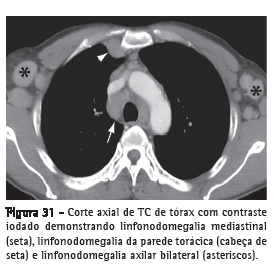

Linfonodomegalia

Aumento de volume de linfonodo de qualquer etiologia, quando suas dimensões ultrapassam os limites considerados normais para a cadeia linfonodal em questão (Figura 31).(52,53) O termo "adenomegalia" não é um sinônimo recomendável, pois linfonodos não são estruturas glandulares verdadeiras. O termo "linfonodopatia" reserva-se para situações onde for possível identificar a doença linfonodal, como, por exemplo, quando se identifica necrose em seu interior.